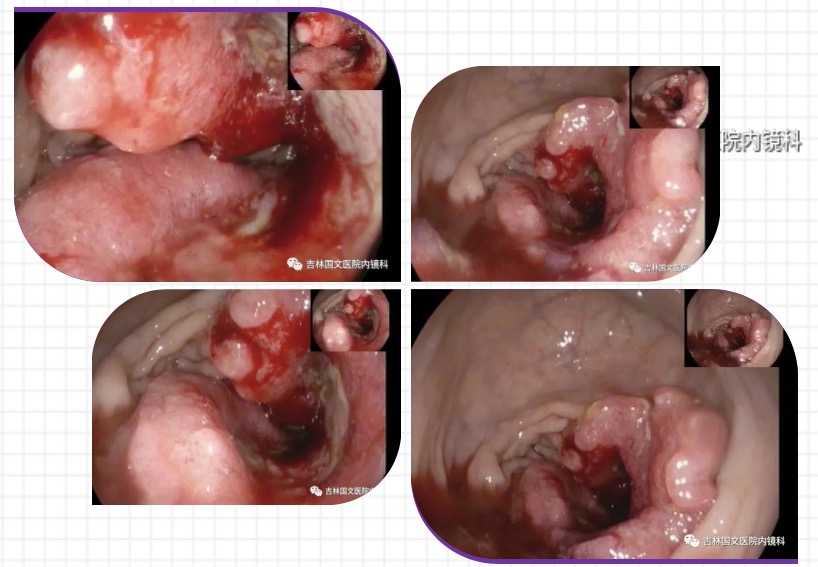

最近就有這樣一起案例,便血后自我診斷為痔瘡,當(dāng)做痔瘡治療了一年多,從未到醫(yī)院詳細檢查過,近日便血加重,腸鏡檢查后,明確診斷為腸癌,被自己的無知和自以為是給害了。

以為是痔瘡 其實是腸癌